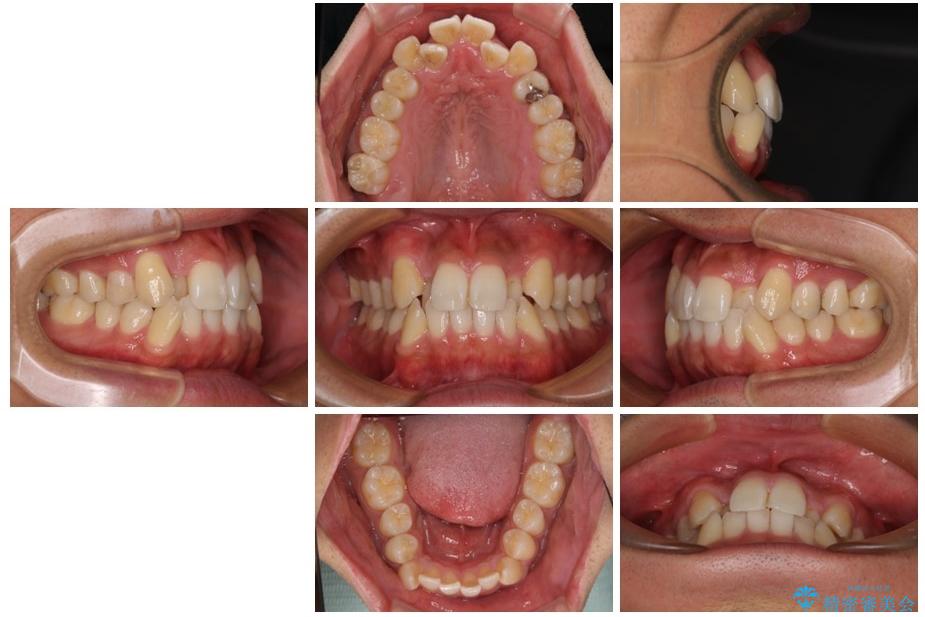

「八重歯を治したい」とご相談いただいた患者様の症例をご紹介します。

上下の前歯部に強い叢生(ガタガタの歯並び)があり、そのまま歯を並べると出っ歯になってしまう可能性がありました。

そこで、上下左右の第一小臼歯を抜歯し、歯が並ぶためのスペースを確保し叢生を解消する治療計画を立てました。

治療前

• 八重歯と前歯のガタガタを抜歯矯正で治療|クリアブラケット使用例 治療前画像